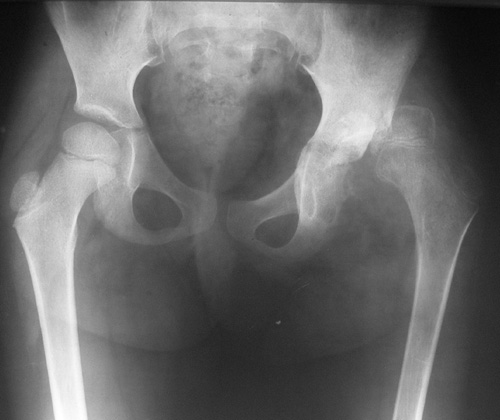

Девочка, 5 лет. Диагноз: Остеохондрома левого тазобедренного сустава.

Поступила 23.07.07. с жалобами на боли и ограничения движений в левом

тазобедренном суставе. Болеет около года, в 2006 г. проходила

стац.лечение с диагнозом левосторонняя коксалгия неясного генеза.

Имя     : before surgery.JPG

Тип     : image/jpeg

Размер  : 53633 байтов

Описание: отсутствует

Url     : http://weborto.net:8080/pipermail/ortho/attachments/20070912/e455cc09/attachment-0002.jpeg